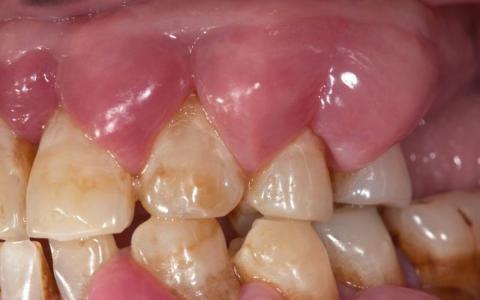

The provided image clearly illustrates an Acute Periodontal Abscess. This is a localized collection of pus (a thick fluid containing dead white blood cells, bacteria, and tissue debris) within the gingival (gum) tissue adjacent to a tooth.

Diagnosis: Periodontal Abscess (sometimes called a gum boil).

Scale All Teeth: The abscess appears localized to the area of one specific tooth (likely a molar or premolar due to the image angle), but the underlying cause is Periodontitis (gum disease), which often affects multiple teeth. A full examination, including X-rays and periodontal charting (measuring pocket depths), is mandatory to assess all teeth and determine the extent of the generalized disease.

Cause: This type of abscess forms when bacteria and debris trapped inside a deep periodontal pocket (the space between the tooth and gum created by advanced gum disease) cannot drain. The infection rapidly progresses, causing the gum tissue to swell and fill with pus.